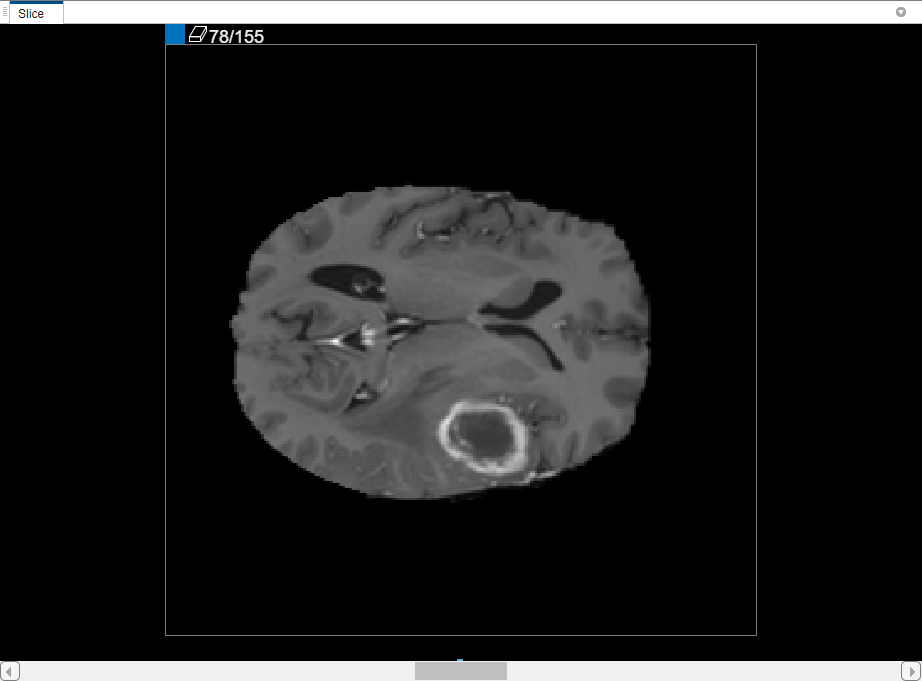

To use interpolation, you must first manually define the region on two slices. You have already defined the region on the first slice where the object appears, slice 35. Use the same process to define the region on the last slice where it appears, slice 88. The app places two bars on top of the slider, using the color associated with the label, to indicate the slices with ROIs.

CreateBinaryMaskUsingVolumeSegmenterExample_06.png

With the object defined on two slices, click Auto Interpolate. The app automatically defines the ROI on all the intervening slides. The app uses blue bars to indicate all the slices that have ROIs, which now appear as a solid bar from slice 35 to slice 88.

CreateBinaryMaskUsingVolumeSegmenterExample_07.png